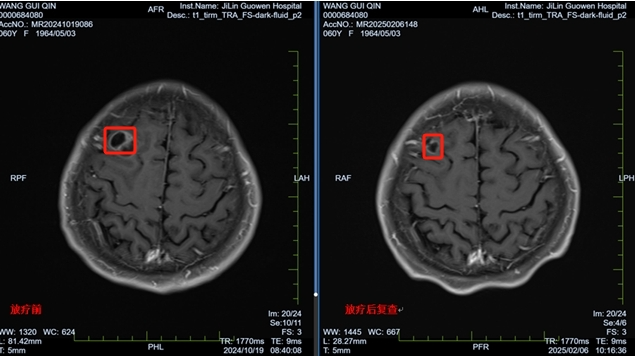

针对王阿姨脑转移的情况,耿光三主任带领团队精心制定了治疗方案,给予缓解脑水肿等对症治疗,针对多个位置的大小不等的脑转移灶,设计了分次立体定向放疗(FSRT)技术进行高剂量照射,精准打击肿瘤。

经过一个疗程的放疗,王阿姨的头痛、恶心等症状明显缓解,精神状态好转。本次复查结果显示,脑部肿瘤明显缩小,病情得到有效控制。王阿姨重新燃起了对生活的希望,乐观面对未来。